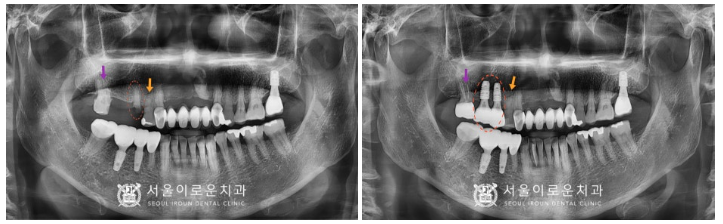

모두 치료를 마무리 한

구강 내 모습입니다.

💛 전 > 후 💛

(2023.11.02ㅡ>2024.04.15)